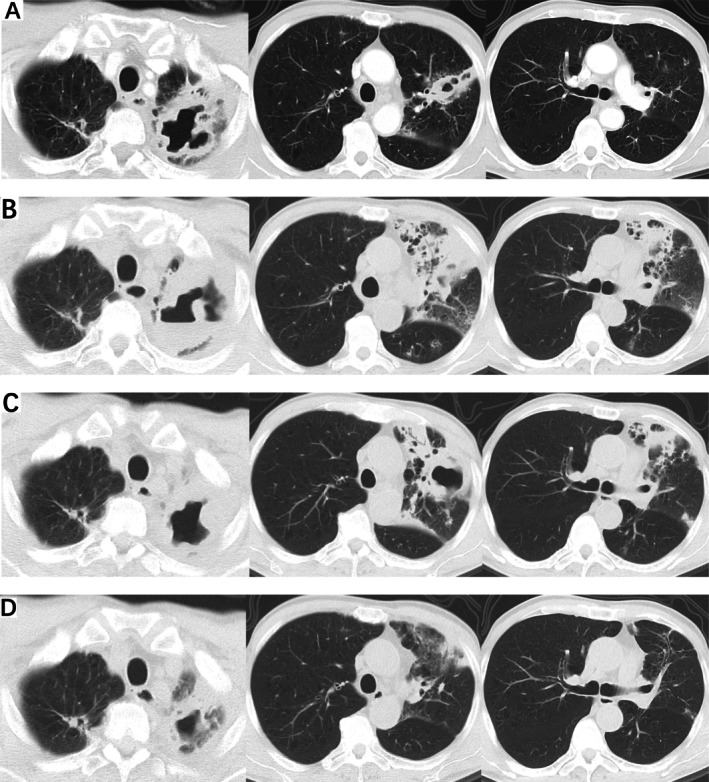

一名64岁男性,有肝细胞癌病史,长期口服lenvatinib治疗,因“咳嗽”两次住院。在住院期间,患者接受了多次支气管镜检查,并送洗液进行病原体检测,结果为阴性。最后,通过下一代测序(NGS)检测到堪萨斯分枝杆菌。考虑到患者肝脏储备不良,我们决定不启动靶向抗菌治疗并停用lenvatinib。停用lenvatinib两个月后,患者咳嗽和胸闷症状有所改善。2025年3月18日随访胸部计算机断层扫描(CT)显示病变消退。

A 64-year-old man, with a history of hepatocellular carcinoma and long-term oral lenvatinib treatment, was hospitalised in our institution twice due to 'cough'. During hospitalisation, the patient underwent multiple bronchoscopies, with lavage fluid sent for pathogen testing, which returned negative results. Finally, Mycobacterium kansasii was detected via next-generation sequencing (NGS). Considering the patient's poor hepatic reserve, we decided against initiating targeted antimicrobial therapy and discontinued lenvatinib. Two months after stopping lenvatinib, the patient's symptoms of cough and chest tightness improved. A follow-up chest computed tomography (CT) on March 18, 2025, showed resolution of the lesions.